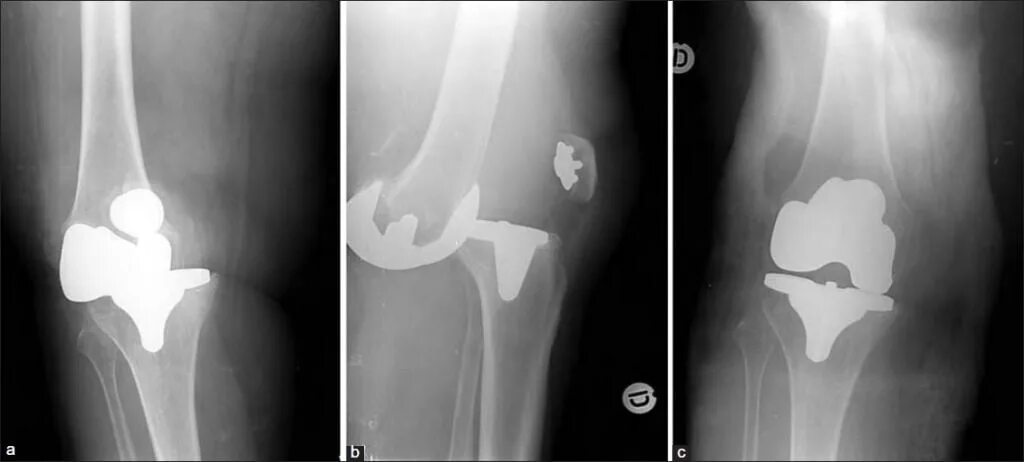

Вывих после эндопротезирования тазобедренного